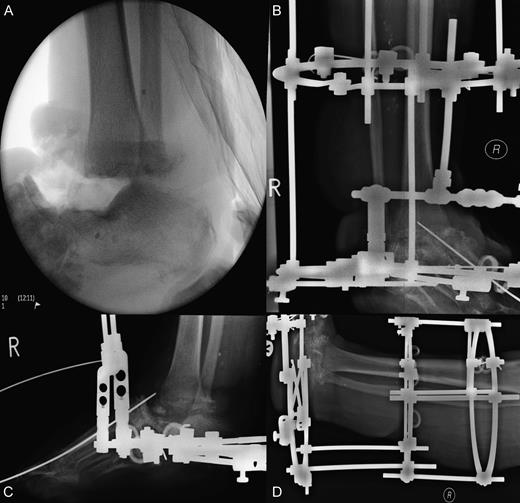

Wound debridement demonstrated pus at screw insertion sites with navicular and talar involvement. The patient had inadequate soft tissue coverage, bony osteomyelitis and necrotic bone. Primary limb shortening with a talectomy was conducted to reduce the soft tissue deficit and remove infected and necrotic bone, tibiocalcaneal arthrodesis for joint stability using external fixation, and dead space was treated with calcium sulphate mixed with vancomycin and systemic intravenous and oral antibiotics for osteomyelitis postoperatively (Figs 3 and 4). The wound was closed after the external fixator was applied. Wound swabs and bone samples revealed Enterococcus faecalis and E. raffinosus and diphtheroids. The patient was treated with intravenous teicoplanin and meropenem with oral stepdown to linezolid and ciprofloxacin.

Surgical images of talectomy and external fixation used for tibiocalcaneal arthrodesis. (A) Anterior posterior intraoperative radiograph illustrating talectomy. (B–D) Radiographs showing external fixation in situ.

External fixation used to facilitate tibiocalcaneal arthrodesis post talectomy. (A) Lateral view (B) Anterior posterior view.